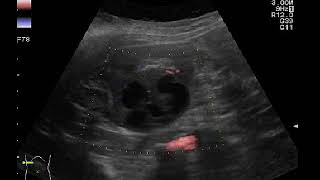

Опухоль может возникнуть в органах, таких как мозг, грудная железа, легкие, желудок, кишечник, почки, печень, предстательная железа и других органах и тканях тела.

Кроме органов, опухоль может образоваться в костях, крови или лимфатической системе. Также она может возникнуть в мягких тканях, таких как мышцы или жировая ткань.